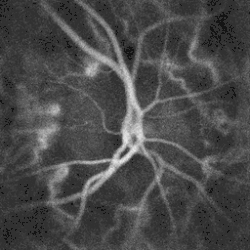

Blood flow in the optic disc revealed by holographic laser Doppler imaging.[4]

Blood flow in the retina and choroid in the optic disc region can be revealed non invasively by near-infrared laser Doppler imaging.[4] Laser Doppler imaging can enable mapping of the local arterial resistivity index, and the possibility to perform unambiguous identification of retinal arteries and veins on the basis of their systole-diastole variations, and reveal ocular hemodynamics in human eyes.[5] Furthermore, the Doppler spectrum asymmetry reveals the local direction of blood flow with respect to the optical axis. This directional information is overlaid on standard grayscale blood flow images to depict flow in the central artery and vein.[6]

Automated techniques have also been developed to allow for more efficient and less expensive imaging. Heidelberg retinal tomography (HRT), scanning laser polarimetry and optical coherence tomography are computerised techniques for imaging various structures of the eyes, including the optic disc. They quantify the nerve fiber layer of the disc and surrounding retina and statistically correlate the findings with a database of previously screened population of normals. They are useful for baseline and serial follow-up to monitor minute changes in optic disc morphology. Imaging will not provide conclusive evidence for clinical diagnosis however, and the evidence needs to be supplanted by serial physiological testing for functional changes. Such tests may include visual field charting and final clinical interpretation of the complete eye examination by an eye care physician. Ophthalmologists and optometrists are able to provide this service.